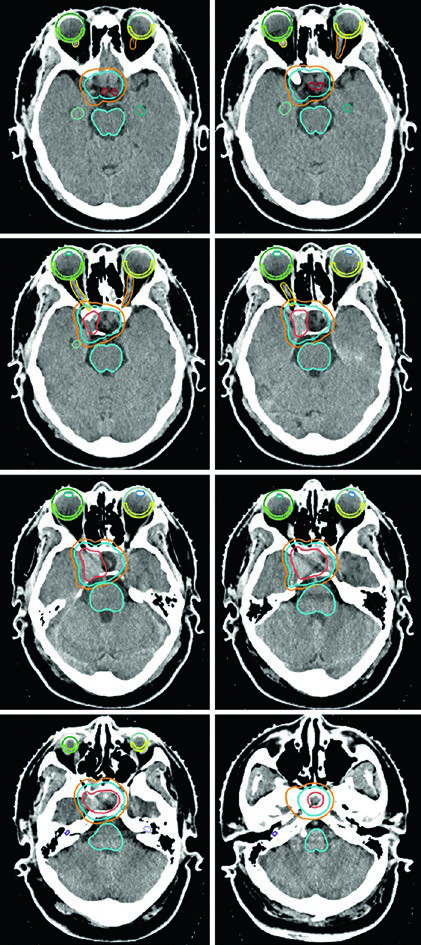

Um ponto prático crucial: a avaliação da TC é essencial para decidir se alterações periosteais e ósseas devem ser incluídas no GTV. No exemplo do meningioma do seio cavernoso (Figura 29.7), o tumor foi delineado com RM de planejamento, recebeu margem de 2 mm para o PTV e foi tratado a 52,2 Gy em 29 frações. As linhas de isodose mostram conformação apertada ao redor do tronco encefálico, quiasma, nervos cranianos adjacentes, artéria carótida e cóclea.

Meningiomas volumosos selares e suprasselares com ressecção incompleta — como na Figura 29.8 — podem requerer expansão de PTV de 3 mm por causa da doença residual extensa. A relação íntima com os globos e o tronco encefálico exige planejamento dosimétrico cuidadoso, frequentemente com IMRT ou VMAT para conformar a dose e proteger essas estruturas.